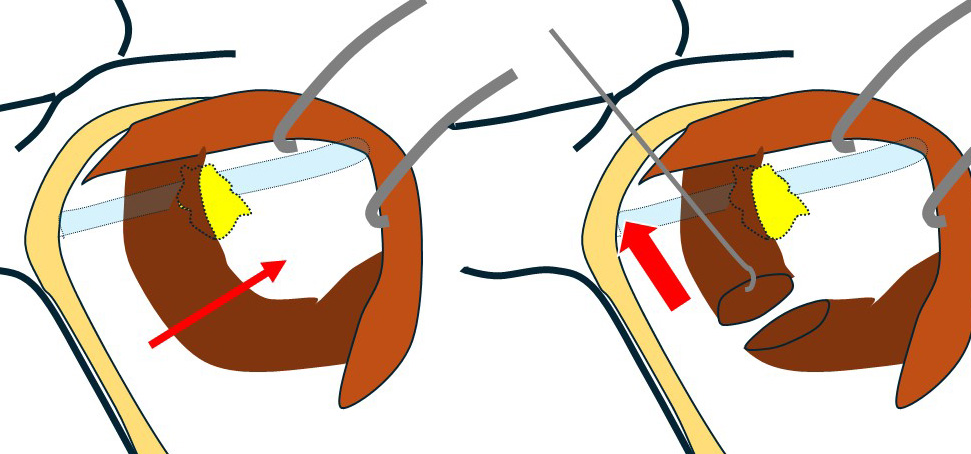

それではどうしたのか?

小胸筋を切断します。(左図)

そして、鎖骨下静脈に被さって視野の妨げとなっている部分を持ち上げます。(右図)

すると…

このように(左図)鎖骨下静脈と鎖骨下リンパ節の関係を(何にも邪魔されずに)直視できる+(鎖骨下リンパ節が持ち上がることによって)「鎖骨下静脈と鎖骨下リンパ節の「接合面」を直視できるのです。(右図)

(矢印のように)慎重に左右から少しずつ外していき、遂に「郭清完了!」となったのです。

小胸筋膜の「こちら側」だけの視野しか持っていなければ(鎖骨下郭清できない乳腺外科医達)とても、その「向こうにあるリンパ節」に手はとどきません。

ましてや、その向こう側で血管に被さって視野を塞いでいるような「鎖骨下リンパ節」の摘出は「夢のまた夢」となるでしょう。

視野の確保が如何に重要か?